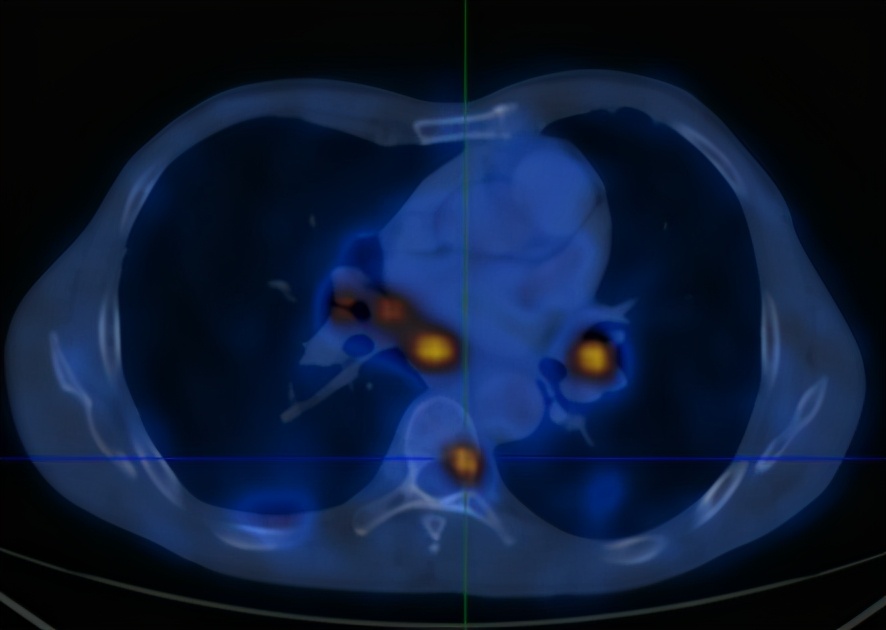

2020-6-19患者行全身PET/CT示:

1、左下肺前内基底段支气管开口处结节,糖代谢增高,考虑中央型肺癌并远端阻塞性炎症、不张;全身(双侧颈部、双侧锁骨上下窝、两侧肺门、纵隔、贲门旁、胰头后方、腹主动脉旁及双侧髂血管旁)多发淋巴结转移;双肺多发转移;肝S4及S5转移;胰头部结节转移;全身多发骨转移;综上,建议活检除外结核。